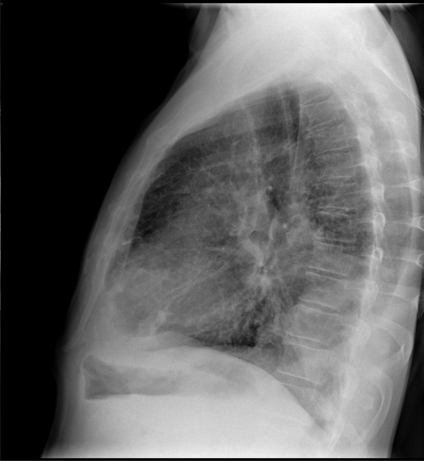

La radiografía simple de tórax es una radiografía del tórax, los pulmones, el corazón, las grandes arterias, las costillas y el diafragma. Es el estudio radiológico más frecuentemente solicitado en el servicio de Urgencias. Su valoración debe realizarse siempre en un contexto clínico apropiado. El estudio radiológico convencional debe incluir, siempre que sea posible, las proyecciones posteroanterior (PA) y lateral (L).

Solicitamos una Rx PA y lateral de tórax, obteniendo las siguientes imágenes: